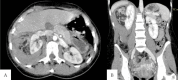

We report the case of a 29-year-old woman with Wunderlich syndrome, a rare spontaneous renal hemorrhage into the subcapsular and perinephric space. She presented to our emergency department with a sudden and persistent right flank pain in the abscence of abdominal injury. The onset of the symptoms can be insidious and lead to hypovolemic shock. Computed Tomography helps both in the diagnosis, detecting the renal hemorrhage, and contributes to an optimal patient management. Selective arterial embolisation is an efficient technique to stop acute and potential life-threatening hemorrhage and preserve the renal parenchyma.